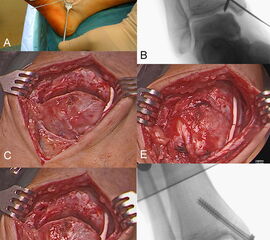

Die autologe Matrix-induzierte Chondrogenese (AMIC ©) wurde erstmals von Behrens et al. (2004) 91 beschrieben. Es ist ein einzeitiges Verfahren auf Grundlage der Knochenmarkstimulation, ggf. mit autologer Spongiosaplastik, und der Abdeckung des Defektes durch eine Kollagen I/III-Matrix. Diese Membran schützt das Regenerat und die darin enthaltenen mesenchymalen Stammzellen 92. In einer Serie von Valderrabano et al. 93 wurden 26 Patienten mit talaren OCLs durch AMIC © behandelt. 17 Patienten wurden zusätzlich mit einer Bandstabilisierung, 16 Patienten zusätzlich mit einer Fersenbein-Osteotomie versorgt. Die 2-Jahres-Ergebnisse anhand des American Orthopaedic Foot and Ankle Society (AOFAS)-Score, der visuellen Schmerzskala (VAS) und des „magnetic resonance observation of cartilage repair tissue” (MOCART)-Scores zeigten überwiegend gute klinische und MRT-Ergebnisse.

Die guten klinischen Ergebnisse wurden auch im Langzeitverlauf von verschiedenen Arbeitsgruppen bestätigt 9495.

Zur Vollansicht und zum Lesen der Bildbeschreibung bitte das Bild anklicken.